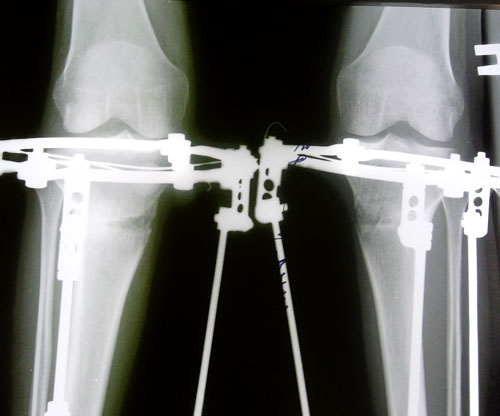

В аппаратах Илизарова-Онипко в день снятия 14.05.2012г.Сразу после снятия аппаратов.

Рентгеновский снимок до операции.Рентген за 3 недели до снятия аппаратов.